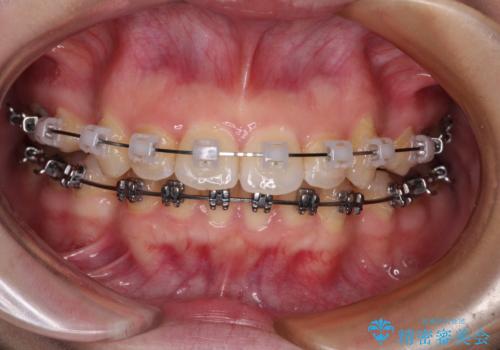

- メタルブラケット

※写真にある上顎装置はメタルブラケットではありません。メーカー在庫都合などにより別の装置を使用しております。